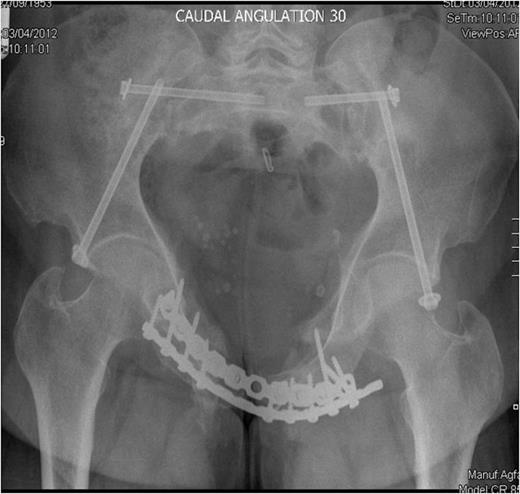

Inlet radiograph at 16 months post surgery demonstrating solid fixation and bony healing

Post-operative recovery was uneventful. Bone and soft tissue biopsies showed no abnormalities. She was kept non weight bearing for 12 weeks. Subsequent dual energy X-ray absorptiometry scanning revealed mild osteopenia for which she is being managed medically. She began full weight bearing at 3 months post surgery. Final follow-up at 16 months demonstrated that the fractures had healed, and the patient was pain free and mobilising unaided (Fig. 3 & 4).

Outlet radiographs at 16 months post surgery demonstrating solid fixation and bony healing